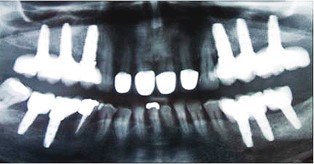

Los implantes dentales son estructuras metálicas que se anclan al hueso maxilar o mandibular, y sobre las que se fijan prótesis dentales. El implante dental es por tanto la raíz del nuevo diente, y la prótesis dental que se pone encima es la nueva corona del diente.

El excelente resultado de estos tratamientos, unido a las mejoras en el diseño y composición química y física de los implantes, ha hecho que actualmente los implantes dentales hayan sustituido a los puentes sobre dientes en casi todas las situaciones clínicas. Es decir, los implantes no se usan sólo en casos muy difíciles, o que son muy complicados de resolver con prótesis convencionales. Ahora los implantes se usan (y es donde más éxito tienen) en los casos "fáciles", en los que hay ausencia de uno o unos pocos dientes, y hay abundante hueso en los maxilares.

Sin embargo, siempre hay muchos factores que se deben tener en cuenta a la hora de diseñar y llevar a cabo un tratamiento con implantes dentales: la salud general y las enfermedades crónicas del paciente, la forma de la arcada dental, la salud de los dientes remanentes, la relación entre el maxilar y la mandíbula, las fuerzas masticatorias de ese paciente en concreto, la cantidad y calidad del hueso donde se van a colocar los implantes, el tipo de prótesis que el paciente va a llevar, etc. Se trata de múltiples y complejos factores.